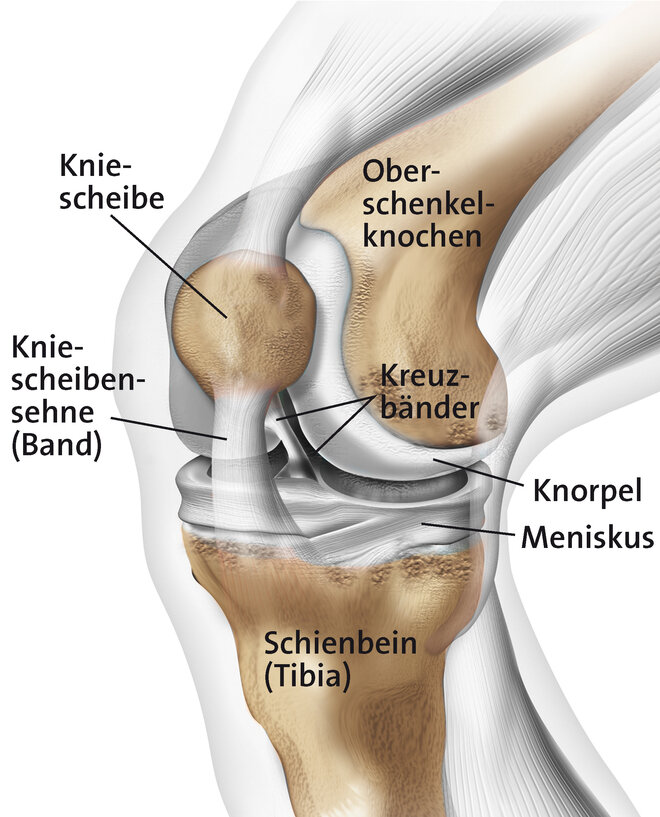

Hintergrundinformation - Das Kniegelenk